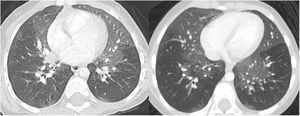

A 3-year-old pediatric patient was referred to our hospital with a history of recurrent respiratory infections and dry nocturnal cough following respiratory bronchiolitis at 5 months. On physical examination, she had mild tachypnea, subcostal and sternal retractions, and some bilateral crackling rales. A chest X-ray showed hyperinflation of both hemithoraxes and increased perihilar density (Fig. 1). Chest computed tomography (CT) scan was performed, showing areas of ground glass density in both lungs, more marked in the lingula and middle lobe (Figs. 1 and 2). An acute respiratory process was assumed, and symptomatic treatment with follow-up was prescribed. In the following months, several studies (autoimmunity, cystic fibrosis, pulmonary scintigraphy) were performed and found to be normal, and several drugs (mucolytics, β2 agonists, corticosteroids, and antibiotic therapy) were administered, but only partial symptomatic relief was achieved. A year later, a new CT was performed that showed persistence of lung findings, at which time the patient was diagnosed with neuroendocrine hyperplasia of infancy (NEHI).

Plain X-ray of the chest (A). Hyperinflation of both hemithoraxes and increased lung parenchyma density in the perihilar region. Chest CT, coronal reconstruction (B). Areas with a ground glass pattern affecting predominantly the middle lobe and the lingula, showing the typical distribution pattern of neuroendocrine hyperplasia of infancy.

NEHI is a type of interstitial lung disease that usually occurs before the age of 2, presenting with tachypnea, crackles, chest retractions, and hypoxemia1,2. The appearance on CT is characterized by a mosaic attenuation pattern with patchy areas and ground glass density affecting 4 or more lobes, typically the lingula and middle lobe. In certain cases, consistent clinical signs and functional tests may permit diagnosis of NEHI without the need for a lung biopsy1,2. The recommended treatment is supportive, with oxygen therapy and prevention measures2.